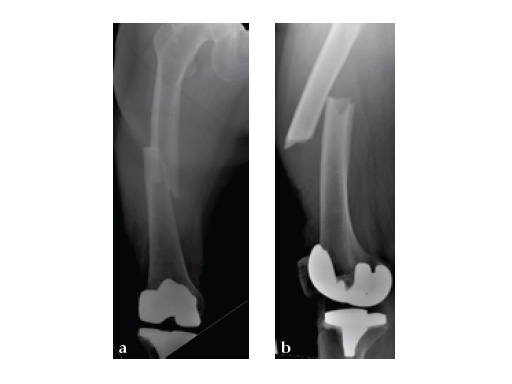

Based on the negative MRI thigh and positive MRI lumbar spine of multiple levels of spinal stenosis, the patient underwent epidural analgesic injection. Patient sustained right femur midshaft periprosthetic fracture the next day after her epidural injection with no trauma.

Notice the fracture decrease the emphasis on the anterolateral bow of the femur (See Fig 5a-b).

Insertion of A2FN as patient may be suffering from a stress fracture related to long term (2.5 years) bisphosphonate use. My rationale against a plate is because bisphosphonate related fractures will heal extremely slowly. In our experience even despite bone grafting union may need up to 2 years. In that time, a plate will fail in less than a year even if the patient is only allowed very minimal weight bearing.

Note despite the increased in curvature compared to other nails in the market, there is still noticeable malreduction at the fracture site (see Fig 6a-b).